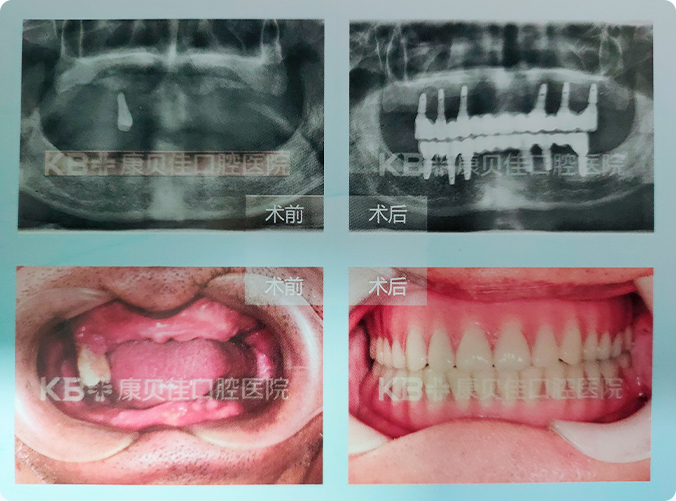

徐先生 57岁

早年患有牙周病,导致牙齿接连脱落。因为牙齿严重缺失,咬不动、嚼不烂,不仅营养跟不上,还连累了健康。到康贝佳拔除了仅剩的一颗重度松动牙之后,采用微创技术在上下牙槽骨中各植入了6颗植体,当天就恢复了满口好牙。

治疗方案:

上颌种植6颗即刻恢复半口 下颌种植6颗即刻恢复半口